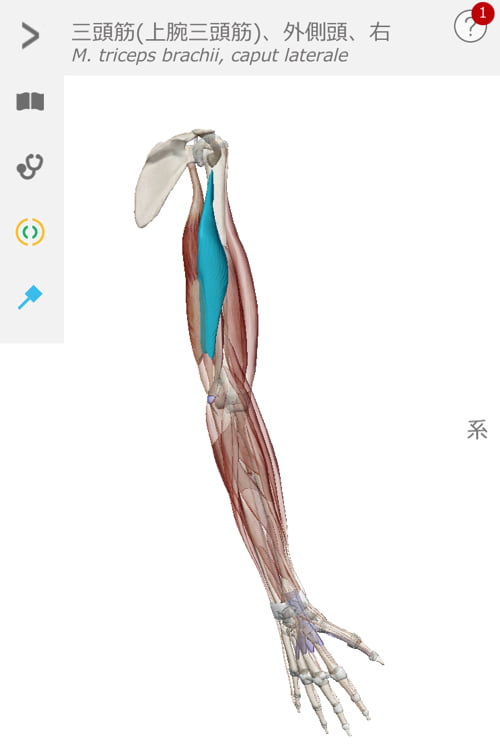

肘がネジレるとこんな感じで繋がっている肩や肩甲骨の位置にずれが生じます。

超精密に出来ている私達の身体はネジレやズレができると

危険回避の為に痛みが出て動かせなくなります。